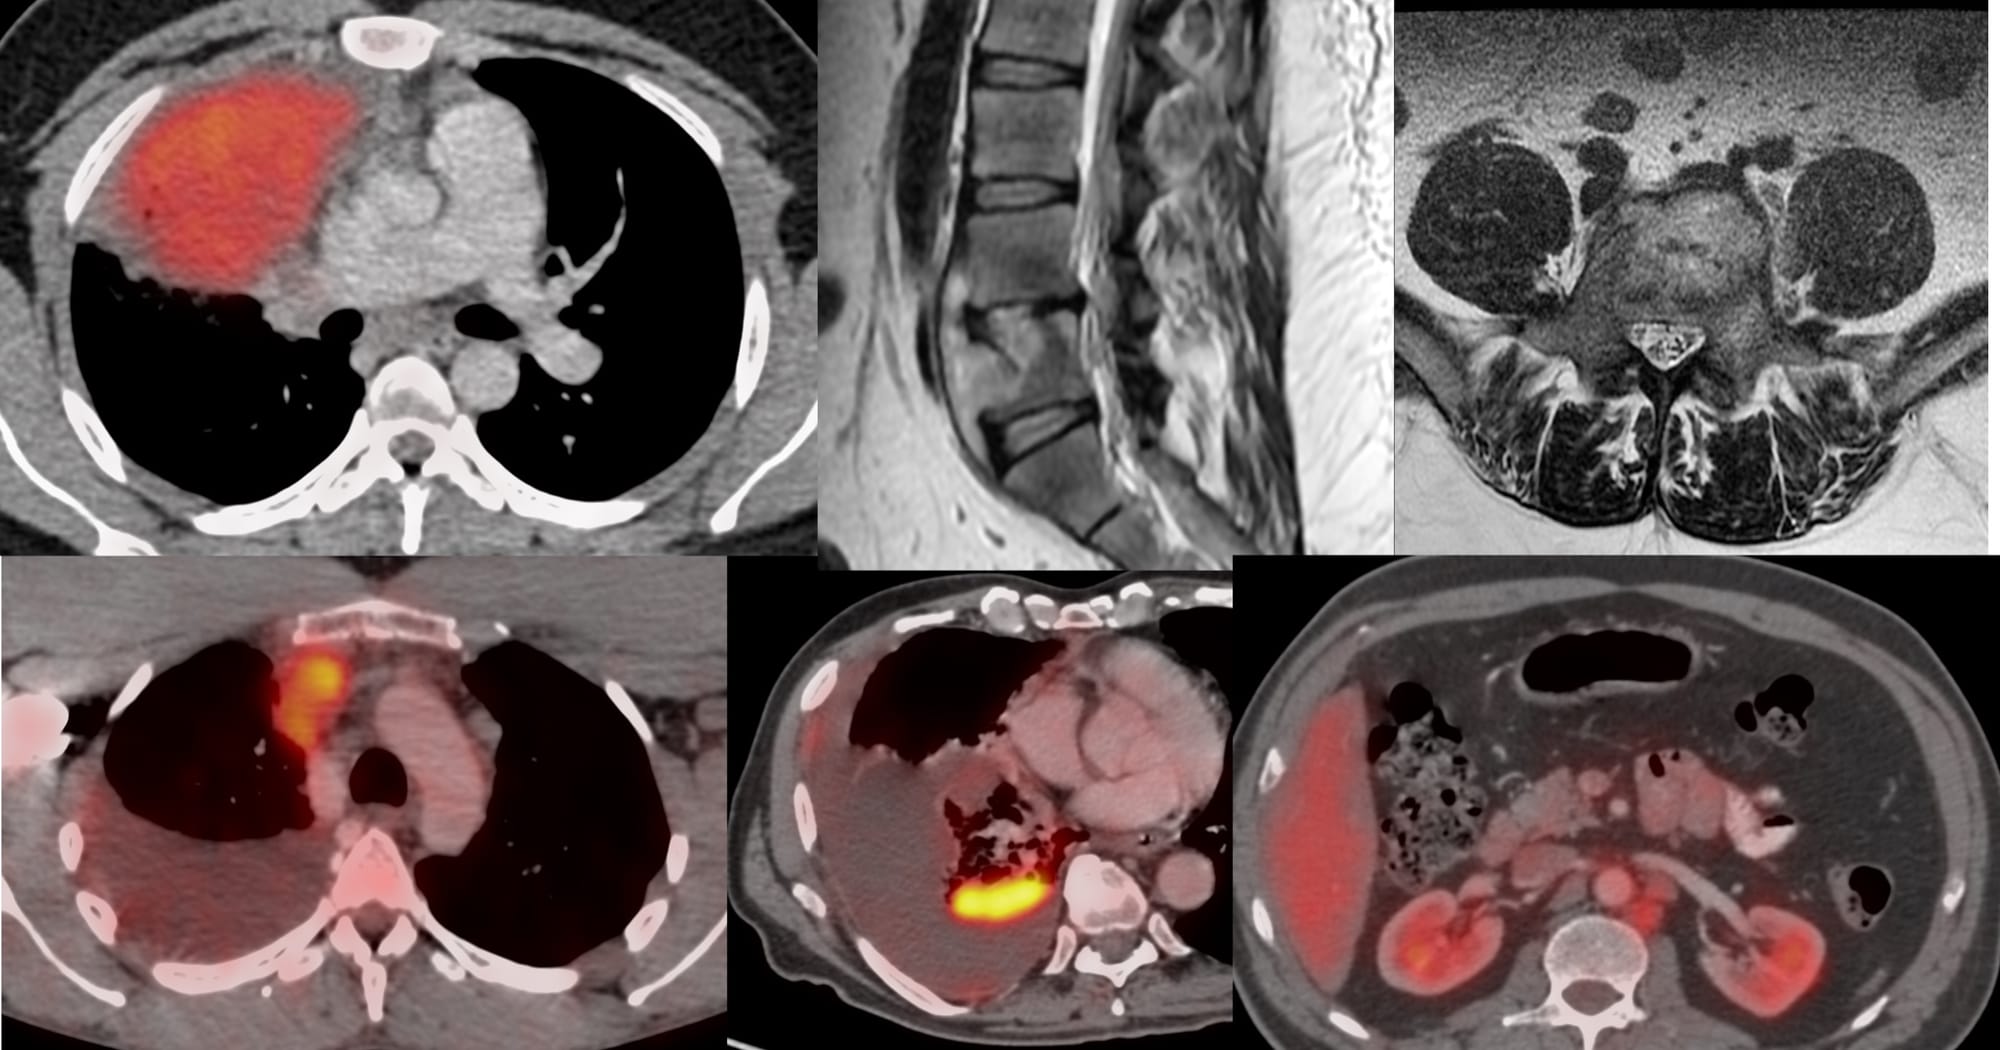

The 6 Cases for YouTube Live on 26 Feb at 7 PM Indian Standard Time

Bhavin Jankharia - 17 February 2026

YouTube Live Session - CT Guided Biopsy Cases from December 2025

Bhavin Jankharia - 10 January 2026

The 7 Cases for YouTube Live on 08 Jan at 7 PM Indian Standard Time

Bhavin Jankharia - 04 January 2026